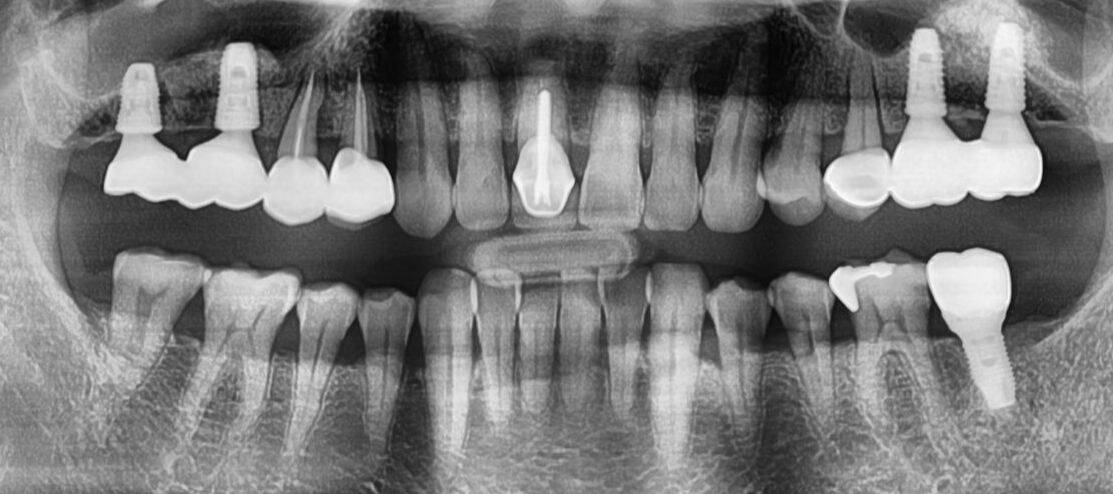

This patient presented with 14 missing teeth, significantly impacting her quality of life. Through a single-session procedure, I successfully placed 12 dental implants. Four months later, she achieved a beautiful, functional smile, restoring her confidence and improving overall oral health.